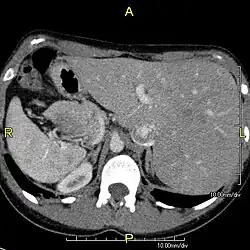

Diagnosis of situs inversus can be made using imaging techniques such as x-ray, ultrasound, CT scan, and magnetic resonance imaging (MRI).[9]

The condition affects all major structures within the thorax and abdomen. Generally, the organs are simply transposed through the sagittal plane. The heart is located on the right side of the thorax, the stomach and spleen on the right side of the abdomen and the liver and gall bladder on the left side. The heart's normal right atrium occurs on the left, and the left atrium is on the right. The lung anatomy is reversed and the left lung has three lobes while the right lung has two lobes. The intestines and other internal structures are also reversed from the normal, and the blood vessels, nerves, and lymphatics are also transposed.

If the heart is swapped to the right side of the thorax, it is known as "situs inversus with dextrocardia" or "situs inversus totalis". If the heart remains on the normal left side of the thorax, a much rarer condition (1 in 2,000,000 of the general population), it is known as "situs inversus with levocardia" or "situs inversus incompletus".

Situs inversus is found in about 0.01% of the population, or about 1 person in 10,000. In the most common situation, situs inversus totalis, it involves complete transposition (right to left reversal) of all of the viscera. The heart is not in its usual position in the left chest, but is on the right, a condition known as dextrocardia (lit. 'right-hearted'). Because the relationship between the organs is not changed, most people with situs inversus have no associated medical symptoms or complications.[1]